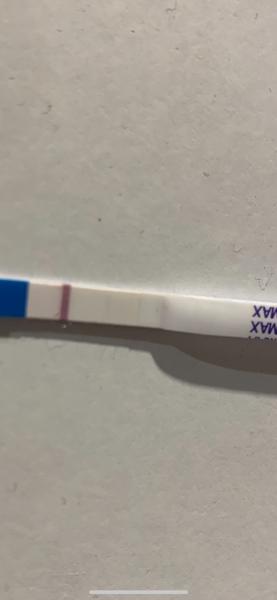

Zdravím, prosím o vaši nynější zkušenost s testy Dr.Max. Během let se jejich kvalita měnila několikrát. Jsem nyní 34.dc tj cca 4dny meškání os obvyklé MS. V tomto cyklu jsem 17. a 18.cd špinila, ale kdy byla ovulace nevím. Dnes jsem si udělala test a po celý limit byl bílý. Pak cca po 1,5hod jsem ho šla vyhodit a je na něm toto. Máte zkušenost s ryskami u tohoto testu po limitu? Děkuji

@vnikan nevím ale pokud je už po limitu tak se to nepočítá ne ? Zkusila bych jiný test,za mě tam druhá čárka je ale pokud je objevila až hodinu a půl po testování nebrala bych na to zřetel a udělala si nový

Děkuji, také jsem právě brala test jako jasně negativní, když do 10min nic neukázal. Ale až po takové době jsem objevila ve skutečnosti hezky viditelnou čárku (do růžova je, zkusím ještě lépe vyfotit). Zkusím ještě další test třeba zítra nebo pozítří..🥴

@vnikan tyto testy mi většinou dělaly rysky, co se objevily po 10 minutách, takže jsem to nebrala. Ale když tam opravdu čárka byla, objevila se hned. Sice hodně slaboučká, ale hned. Ovšem nešla takhle pěkně vyfotit, jako tvoje. Takže si vlastně neporadím 😅 ale budu držet palce, ať to dopadne 😊

@vnikan na začátku se může objevit čárka i po limitu ,prostě je to pozitivní,zkuste obden další tt,čárka musí sílit

Byly nejlepsi a kdyz ukazal ducha, tehotna jsem byla. Ale tohle vypada jako ryska